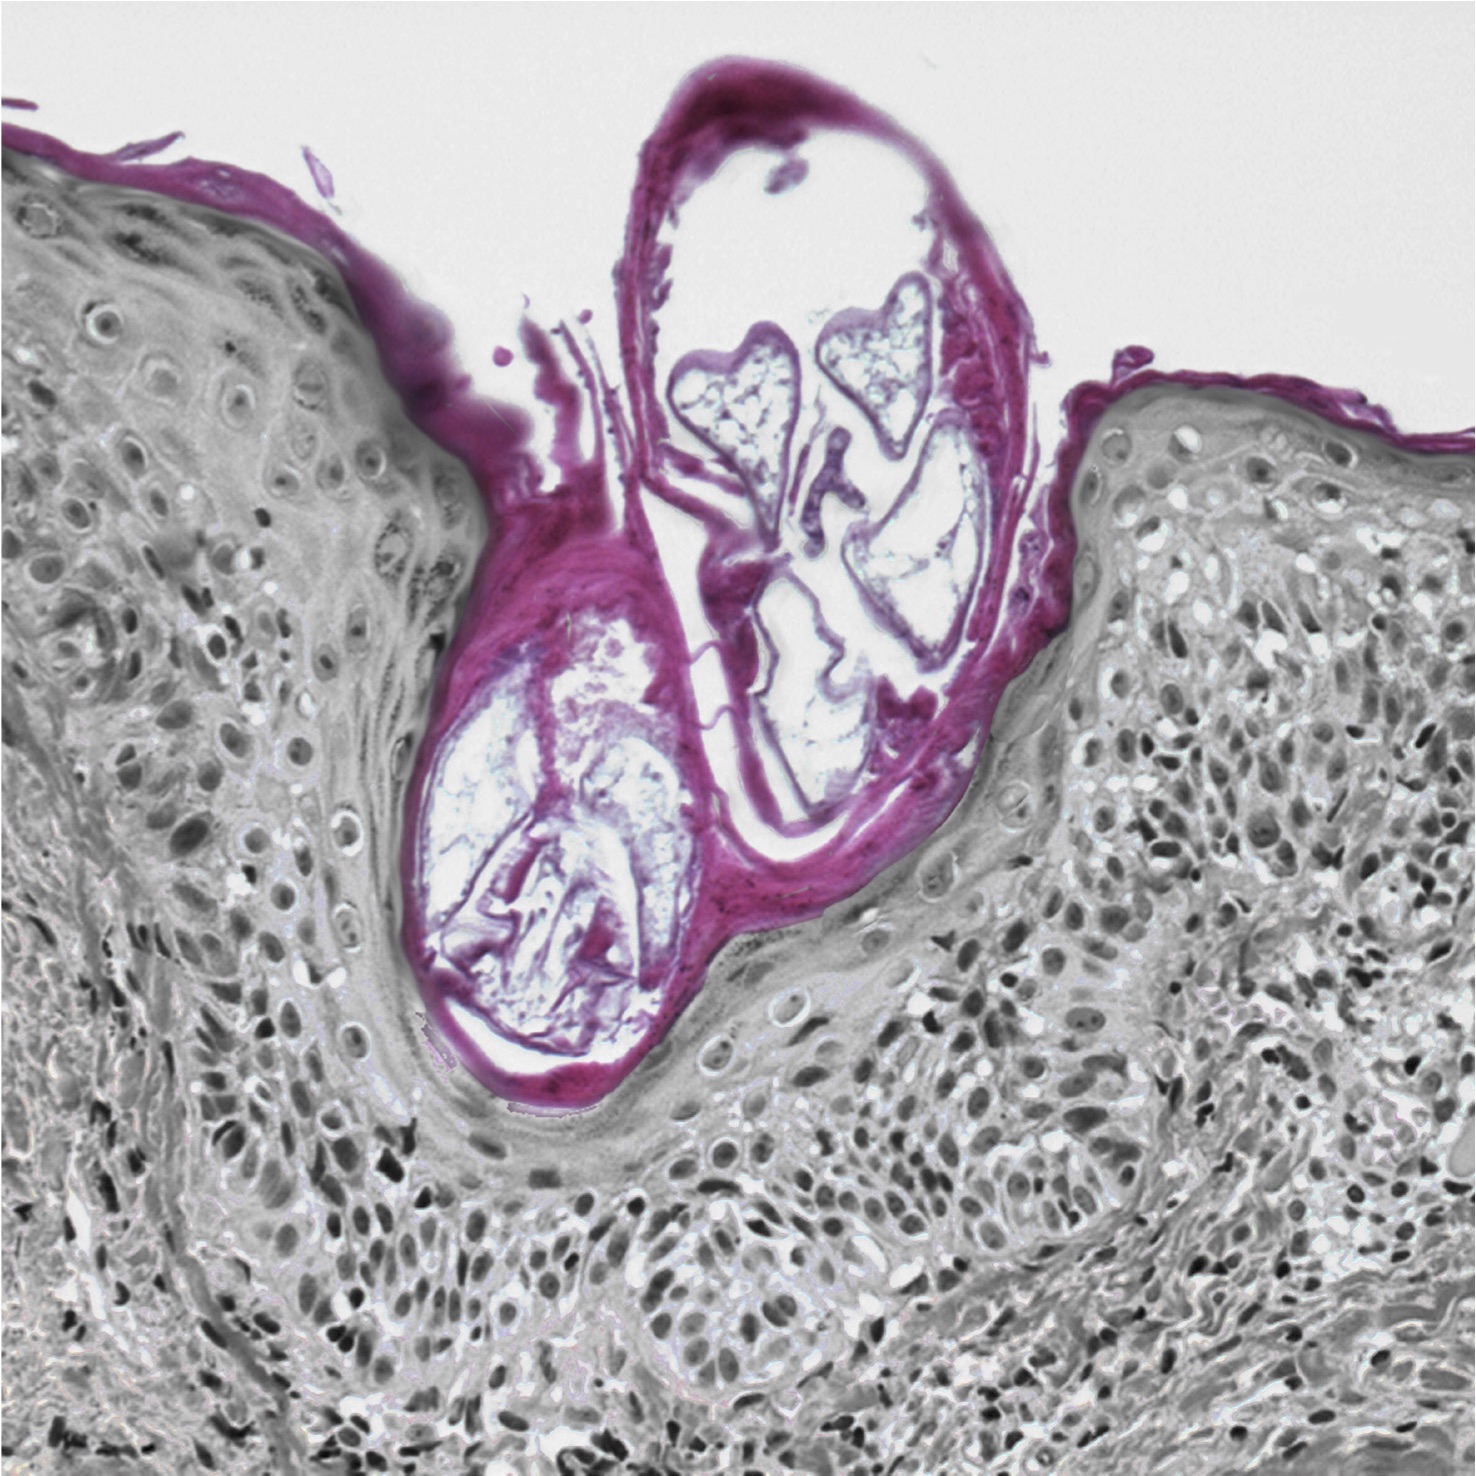

Les artefacts sont très fréquemment rencontrés dans le domaine de l’anatomo-pathologie, spécialité médicale ayant pour but l’analyse des cellules et tissus humains à partir de multiples préparations : étalement, apposition, inclusion, coupe et colorations variées.

Les prises de vues ici présentées correspondent à des images choisies non pas avec le regard du praticien cherchant les indices dans le but de fournir un diagnostic mais avec un regard se voulant uniquement esthétique. En effet, ces clichés plus ou moins retravaillés sont issus d’une seconde lecture de véritable cas dont les préparations ont pourtant été faites initialement dans un but diagnostique.

Les artefacts qui ont été photographiés sont la conséquence de phénomènes multiples. Il s’agit pour les préparations cytologiques de réalisations faites par le médecin-préleveur qui réalise de manière inconsciente chaque jour et pour chaque patient une œuvre unique qui ne sera finalement révélée voire magnifiée que dans les services d’anatomie pathologique. Il s’agit également de petits défauts survenus au cours des différentes étapes de la préparation par les techniciens de laboratoire assez anodins pour ne pas empêcher l’interprétation des images mais suffisants pour créer une illusion. Il s’agit enfin d’images construites par le plan de coupe ou la prise de coloration par le matériel tissulaire réalisant au final une forme irréaliste ou un contraste atypique. L’ensemble de ces images est le plus souvent négligé, n’ayant pas d’intérêt scientifique ou médical. Elles peuvent pourtant laisser de temps en temps, s’évader l’esprit du pathologiste, l’espace de quelques instants, en proie à l’illusion, au mirage qu’elles suscitent.

Ainsi, chacun d’entre nous peut se laisser aller à l’émerveillement devant la beauté de la nature, à l’échelle de l’infiniment petit, avec l’immense richesse de formes et de couleurs dont revêt le corps humain.